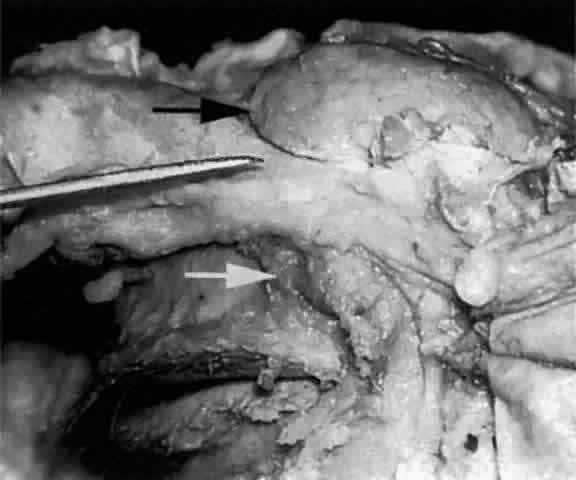

The main lacrimal gland resides in the superotemporal orbit, partially within a shallow bony fossa in the lateral angular process of the frontal bone (fossa glandula lacrimalis). The gland is situated between the eyeball below and the curved orbital wall above, giving it a somewhat compressed and curved shape. It may extend inferiorly to the lateral canthal tendon. The lateral horn of the levator aponeurosis crosses the gland anteriorly, separating it into a larger superior or orbital lobe and a smaller inferior or palpebral lobe (Fig. 2). The division is incomplete because the larger orbital lobe is connected to the smaller palpebral lobe posteriorly by a bridge of glandular tissue, draining tubules, and Müller's muscle, which is attached to the underside of the levator muscle and aponeurosis. The lacrimal gland is surrounded by fibrous tissue that is attached superiorly to the periosteum of the frontal bone and inferiorly to the orbital portion of the zygomatic bone.1

Fig. 2. With the roof and lateral wall of the left orbit removed, this cadaver dissection demonstrates the orbital lobe (black arrow) and the palpebral lobe (white arrow) separated by the lateral horn of the levator aponeurosis (pointer).

These attachments may become attenuated in older persons, allowing the gland to herniate through a weakened orbital septum to give a temporal bulge in the upper eyelid (Fig. 3). The lacrimal gland tissue is usually grayer and pinker than the surrounding yellow adipose tissue.